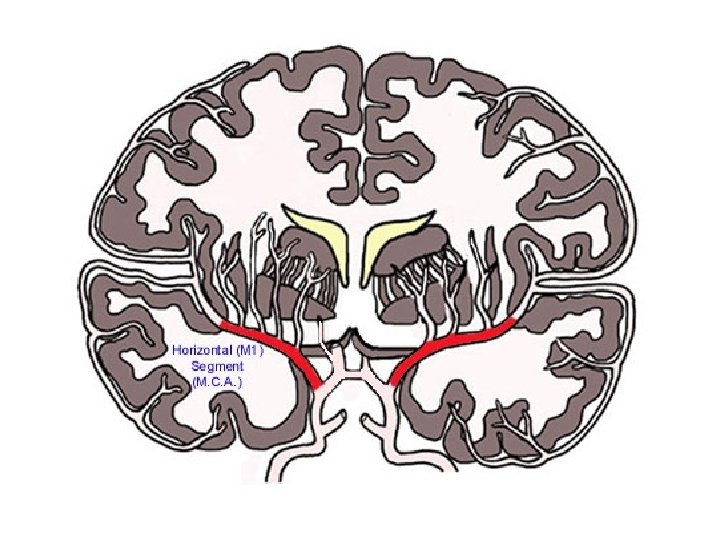

Supplies most of the temporal lobe, anterolateral frontal lobe, and parietal lobe. Perforating branches supply the posterior limb of the internal capsule, part of the head and body of the caudate and globus pallidus.

Unilateral occlusion of MCA at the stem (proximal M 1 segment) results in: • Contralateral hemiplegia affecting face, arm, and leg (lesser). • Homonymous hemianopia - Ipsilateral head/eye deviation. • If on left: global aphasia. • Usually occlusion is embolic in nature - thrombotic occlusion more common in carotids.

Branch of M 1 Segment of MCA. Supplies basal ganglia structures: Part of head and body of caudate, globus pallidus, putamen, and the posterior limb of the internal capsule.